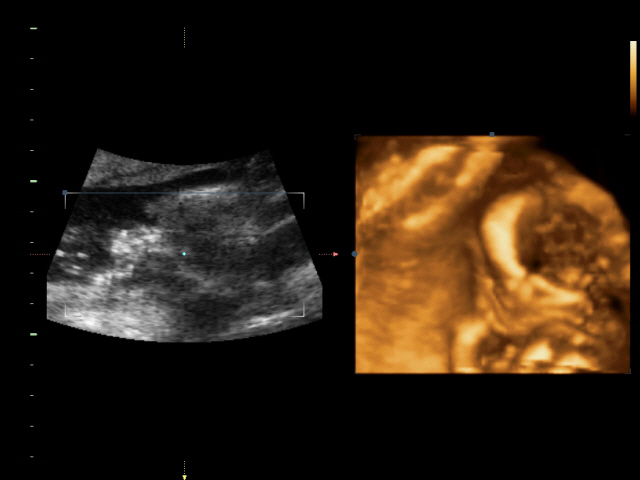

УЗИ, КТГ, доплерСходили всей семьей на 4D УЗИ! Определили нам пол окончательно и бесповоротно! Мальчик! Показали писюн! Так здорово! Я просто поверить не могу! А ведь он мне два раза снился! Настоящий реальный мужчина! Все показатели у нас в норме.